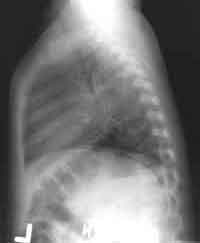

Enlarge the CHEST X-RAY LEFT, enlarge the CHEST X-RAY RIGHT.

WHAT

IS YOUR INTERPRETATION OF THE XRAYS?